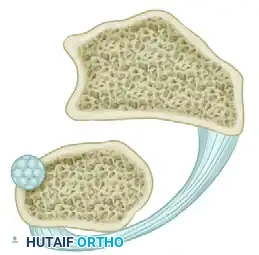

* A small tendon graft is harvested.

* The graft is looped circumferentially around the neck of the ulna to act as a neo-ligament.

Figure: An annular ligament is formed by looping the small tendon graft around the neck of the ulna and preparing it for attachment to the radius.

Step 3: Radial Attachment

* Drill holes are created in the ulnar aspect of the distal radius.

* The free ends of the tendon graft are passed through the radius to secure the ulnar loop, effectively tethering the ulna to the sigmoid notch.